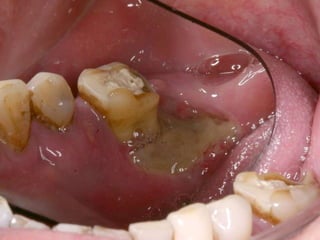

25 - L.C.S., sexo masculino, 18 anos de idade, se apresentou com queixa de aumento de volume na gengiva entre os dentes 23 e 24. Pelo exame clínico, constatamos a presença de um nódulo séssil, de contornos irregulares, coloração avermelhada, com sangramento abundante ao mínimo toque e evolução de 1 ano. O paciente apresentava higiene bucal precária com presença de placa bacteriana e tártaro. Com base no quadro clínico, o diagnóstico é: a) Fibroma e granuloma piogênico. b) Granuloma piogênico e hiperplasia fibrosa inflamatória. c) Lesão periférica (granuloma) de células gigantes e fibroma. d) Granuloma piogênico e lesão periférica (granuloma) de células gigantes. e) Hiperplasia fibrosa inflamatória e fibroma.

Granuloma Piogênico LesãoNodular Séssil ou pediculada Avermelhada ou vinhosa Sangramento espontâneo e áreas de micro-ulceração superficial

Granuloma Piogênico Lesõesnodulares de coloração avermelhada ou vinhosa Provavelmente uma reação inflamatória exagerada ao trauma menor Crescimento rápido, às vezes sangramento espontâneo Ocorre em qualquer idade mas parece mais freqüente em adultos jovens e adolescentes Localização mais comum: gengiva (NEVILLE,2001)

Granuloma Piogênico Lesõesmais antigas, são menos vasculares e mais fibrosas Papila interdental e regiões anteriores são áreas preferenciais, principalmente por vestibular (BORK,1996)

Granuloma Periférico deCélulas Gigantes Lesões nodulares de coloração avermelhada ou vinhosa Provavelmente uma reação inflamatória exagerada ao trauma menor Crescimento rápido, às vezes sangramento espontâneo Ocorre em qualquer idade mas parece mais freqüente em homens antes dos 16 anos de idade a após esta faixa torna-se duas vezes mais freqüente em mulheres Localização mais comum: gengiva

Granuloma (Lesão) Periféricode Células Gigantes A excisão cirúrgica deve ser antecedida de exame radiográfico, pois lesão não completamente removida e/ou com infiltração óssea, pode recorrer